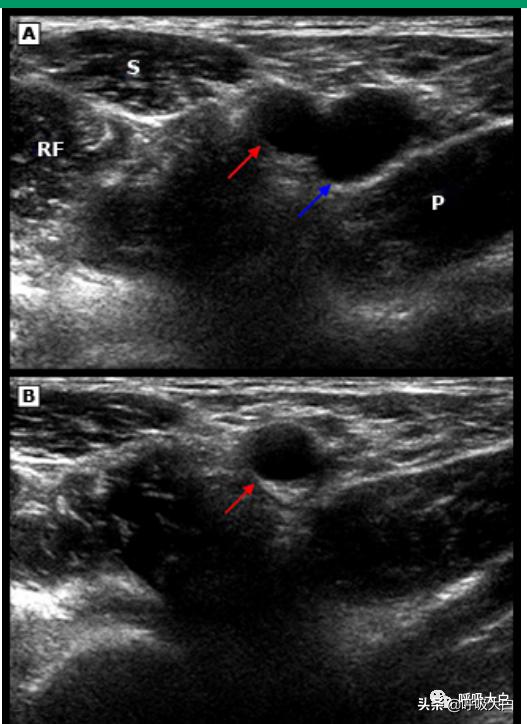

●为探头的外部包裹物涂抹无菌超声传导介质,如水溶性润滑剂。在超声屏幕(横切面)上识别股静脉并使其位于屏幕中央,也可采用纵切面图像,但要仔细区分动脉和静脉(影像 1)。

●如果横切面上难以看到针尖,则在组织中上下轻柔地摇动穿刺针以帮助识别穿刺针。在横切面上,调整超声束以聚焦在针尖上而不是针杆上很重要。未能这样做可导致不慎刺到更深层的结构。